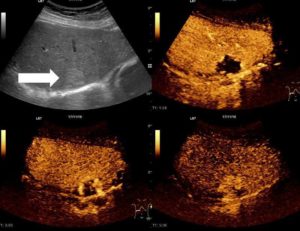

Если диагностирован гепатит С, то пациенту назначается дополнительное УЗИ с цветным допплеровским картированием. Такая разновидность ультразвукового исследования позволяет специалистам проследить работу сосудов, которые питают железу, ток крови в динамике. Этот метод дает возможность отследить движение крови по сосудам печени в реальном времени и в цветном изображении.

Специалист диагностики увидит направление движения жидкости и скорость, а также отследит места, где кровоснабжение отсутствует.

УЗИ в сочетании с ЦДК (цветным допплеровским картированием) — это один из самых информативных, востребованных и распространенных видов диагностики заболеваний печени.